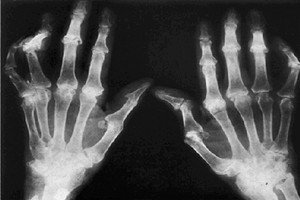

随着类风湿性关节炎在日常生活中发病率的逐年上升,相信生活中肯定有不少的患者朋友们对于类风湿性关节炎的治疗问题都非常的关注。那么,怎么治疗类风湿性关节炎呢?请看下文的详细介绍。

外科治疗就是我们一般所说的手术治疗,目前临床上采用手术治疗类风湿性关节炎疾病的患者确实不少,这是针对于病情发展较重的一些患者。目前对仅有1~2个关节受损较重、经水杨酸盐类治疗无效者可试用早期滑膜切除术。后期病变静止,关节有明显畸形病例可行截骨矫正术,关节强直或破坏可作关节成形术、人工关节置换术。负重关节可作关节融合术等。